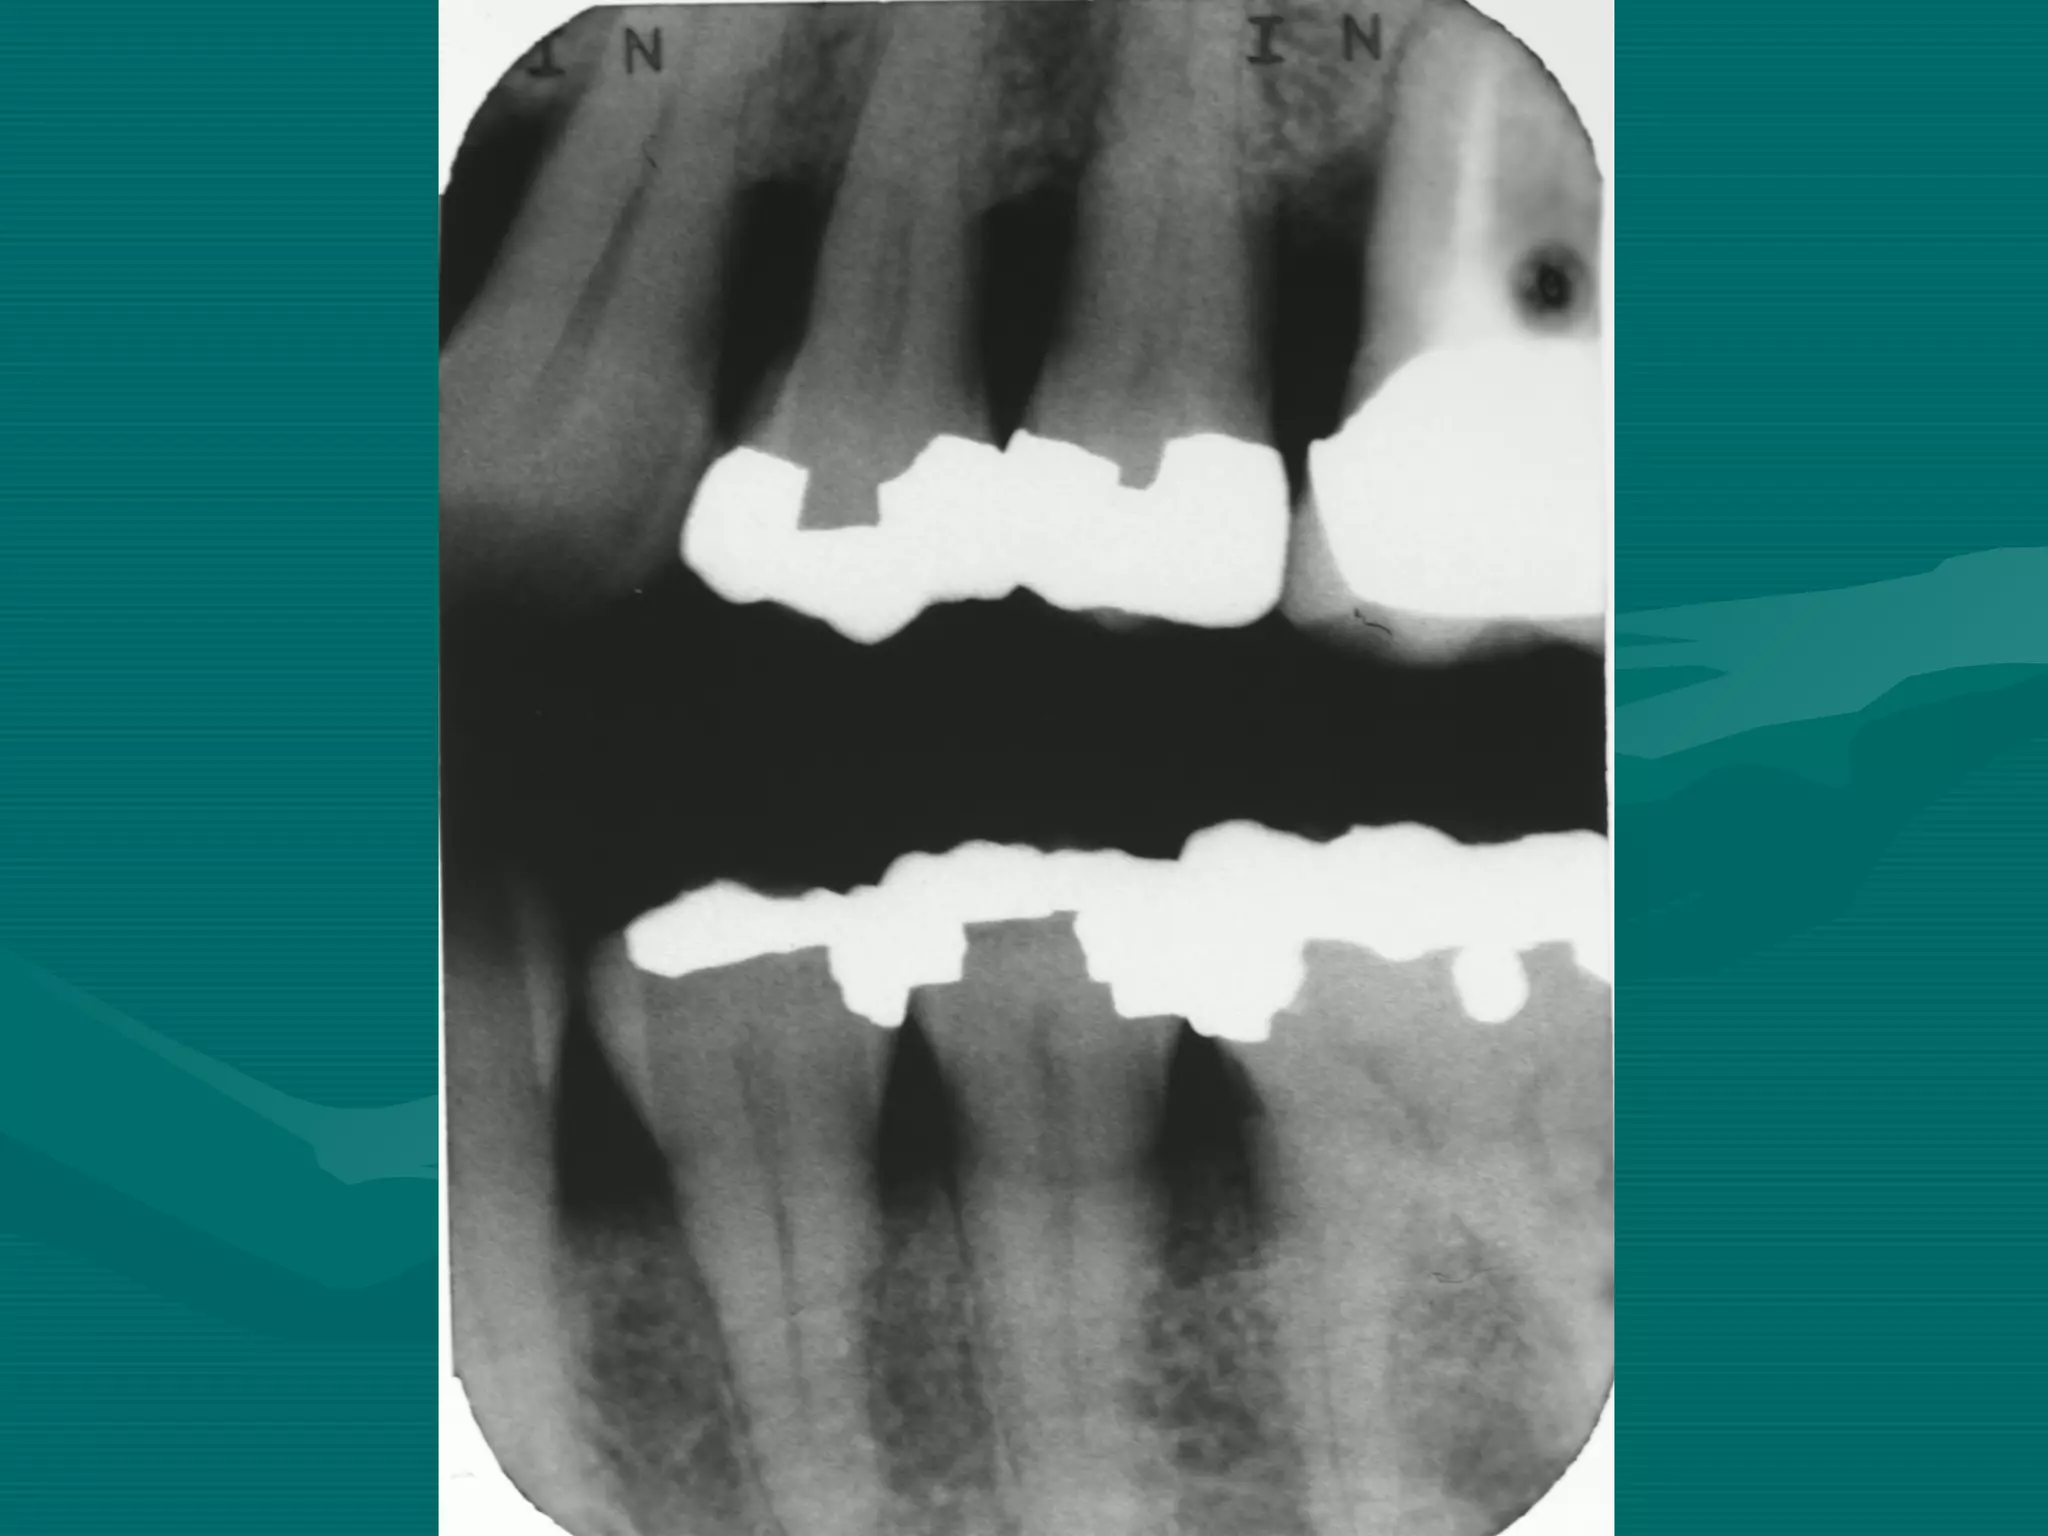

BITEWING

ERRORS

Bite-wing Technique ErrorsBite-wing Technique Errors

Patient is not biting on the bite block

Film placement

Film bending

Horizontal angulation

Single overlap. Technique OK

Cone cut

Film Reverse